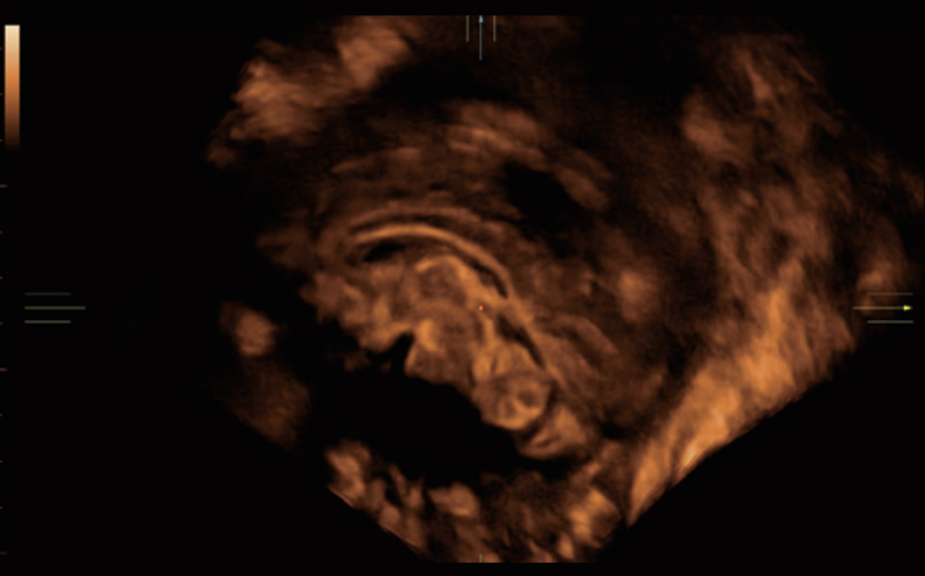

El sistema Nuewa I9, dise?ado exclusivamente para la atenciĂłn mĂ©dica neonatal y de mujeres, brinda una experiencia innovadora integral. Estas innovaciones se desarrollan sobre la base de un conocimiento profundo de situaciones clĂnicas complejas para proporcionar respuestas precisas y oportunas, una gran eficiencia y una experiencia de usuario extraordinaria.

SoluciĂłn completa con tecnologĂa de ZST +

La plataforma ZST+?es una innovaciĂłn extraordinaria que representa toda una evoluciĂłn en el ĂĄmbito de la ecografĂa. Transforma las mĂ©tricas ecogrĂĄficas de la formaciĂłn de haces convencional al procesamiento basado en datos de canal. Supera la limitaciĂłn tradicional de tener que equilibrar entre resoluciĂłn espacial, resoluciĂłn temporal y uniformidad del tejido, con lo que ofrece una calidad de imagen excepcional para soluciones de producciĂłn de imĂĄgenes infinitas con mejoras continuas.